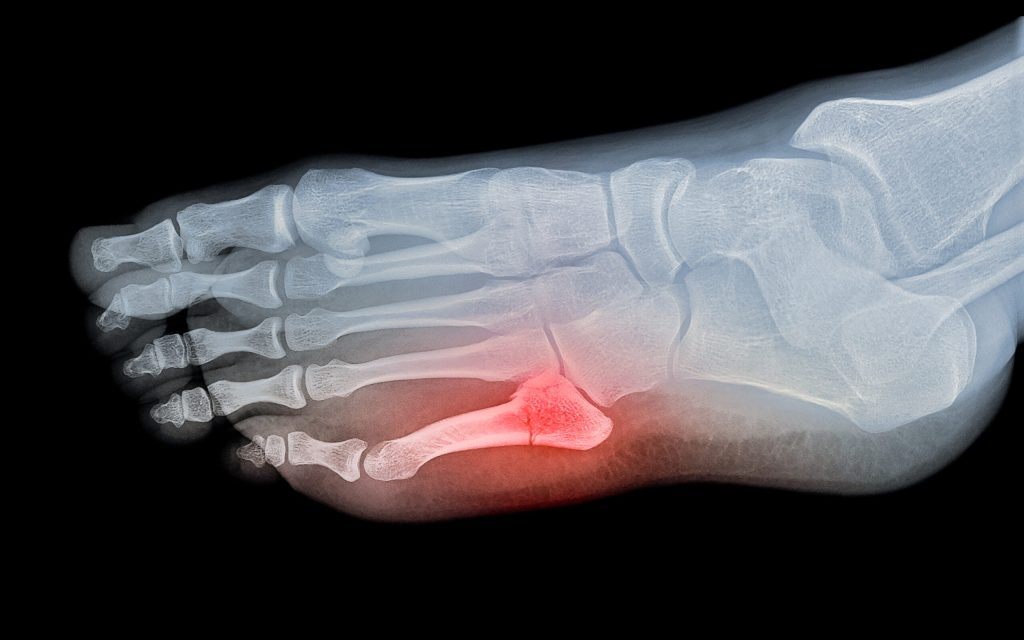

How Is a Stress Fracture Diagnosed?

Diagnosis is based on clinical examination and imaging tests:

- Physical exam focusing on tenderness and swelling

- X-rays may not show early stress fractures; they are more useful a few weeks after symptom onset

- MRI or bone scans are more sensitive and can detect stress fractures early

- Sometimes CT scans are used for detailed images